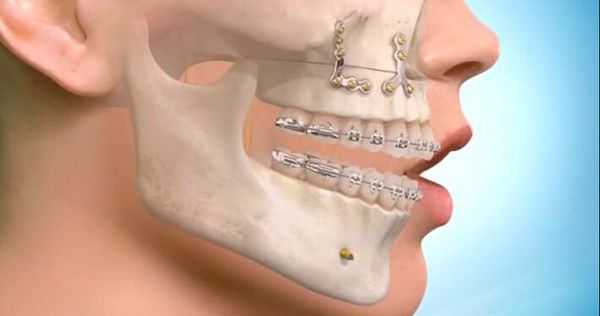

Лечение перелома нижней челюсти заключается в сопоставлении отломков и их фиксации. Иммобилизация обеспечивается проволочными назубными шинами, проволочными или полимерными нитями, остеосинтезом металлическими стержнями, а также с помощью специальных аппаратов. Раны ушивают, при обширных дефектах накладывают проволочные пластиночные швы. Важно обеспечить питание больного высококалорийной пищей, вводимой с помощью поильника или чайной ложки. Для предотвращения травматического остеомиелита вводят антибиотики.

- При госпитализации в стационар применяется лечебная иммобилизация, методом выбора является двучелюстная индивидуальная шина Тиггерштедта с зацепными петлями для межчелюстной фиксации, либо стандартная шина Васильева.

Хирургическое вмешательство. Смещение отломков осложняются мышечной интерпозицией, что является прямым показанием к остеосинтезу.

Существуют различные способы внутрикостного и накостного оперативного закрепления отломков нижней челюсти и их сочетаний, фиксирующее отломки устройство может соединять их концы, пересекая щель перелома, проходя внутри кости.

Оно может прилежать к ее компактной пластинке или частично входить в кость (прямой остеосинтез). Прямой остеосинтез предполагает рассечение мягких тканей и обнажение концов костных отломков (за исключением закрытого введения спиц) с последующим ушиванием раны наглухо. Фиксирующее приспособление полностью закрыто мягкими тканями.